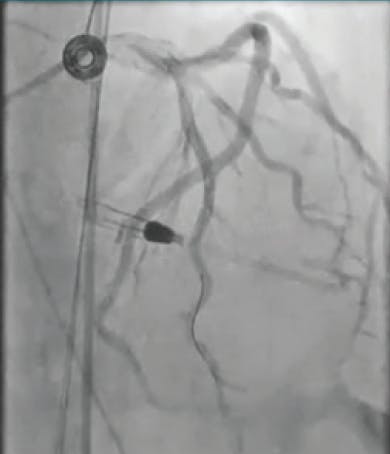

Angiography showed complete occlusion and heavy thrombus burden from the SVG to the diagonal branch (Figure 1). It was planned to intervene upon the lesion. The occlusion was determined to be acute based on a previous angiogram within the past month that showed a patent SVG to the diagonal branch. The lesion was wired using a 0.014-inch X 300-cm Sion® Blue wire (Asahi Intecc USA, Inc.) without any problems. Because the graft was totally occluded, it was decided not to advance a filter through the occlusion due to risk of distal embolization (Figure 2). Mechanical thrombectomy with CAT RX was used to aspirate the thrombus. After three runs of mechanical aspiration using a CAT RX and around 3 minutes of aspiration, TIMI 3 flow was restored (Figure 3). The patient was treated with heparin infusion overnight to reduce further thrombus burden and was brought back to the catheterization laboratory the next day for staged PCI with a DES (Figure 4).

Figure 1. Initial angiogram showing occlusion through the SVG.

Figure 2. Angiogram after wiring.

Figure 3. TIMI 3 flow through the SVG after using CAT RX.

Figure 4. Final angiogram after using CAT RX and staged PCI.